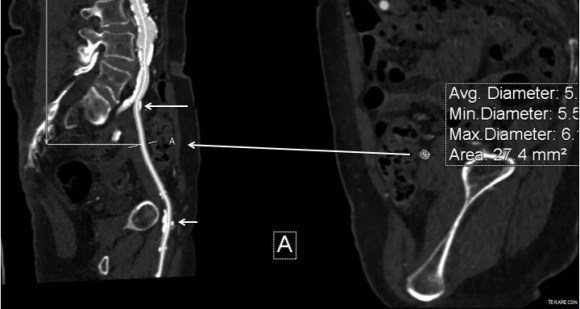

This patient presents with lifestyle limiting claudication and an absent right femoral pulse. ABI is moderately reduced on the right to 0.57, and he had no rest pain. CTA at our clinic revealed an occluded EIA bracketed by severely calcified and nearly occlusive plaque of the common iliac artery (CIA) and common femoral artery (CFA).

The patient was amenable to operation. Traditionally, this would have been treated with some form of bypass -aortofemoral or femorofemoral with a common femoral endarterectomy. While endovascular therapy of the occluded segment is available, one should not expect the patencies to be any better than that of occlusive lesions (CTO’s) in other arteries. Hybrid open/endovascular therapy is an option as well with CFA endarterecotmy and crossing CIA to EIA stents, but I have a better solution.